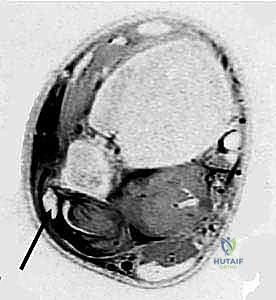

- الموجات فوق الصوتية الحركية (Dynamic Ultrasound): تقنية ممتازة تتيح للدكتور رؤية الوتر وهو ينزلق خارج مكانه أثناء حركة المريض المباشرة.

- الرنين المغناطيسي (MRI): هو المعيار الذهبي. يوضح بدقة متناهية شكل الميزاب العظمي، حالة القيد الليفي (SPR)، وما إذا كان هناك تمزق طولي مصاحب في الأوتار نفسها.